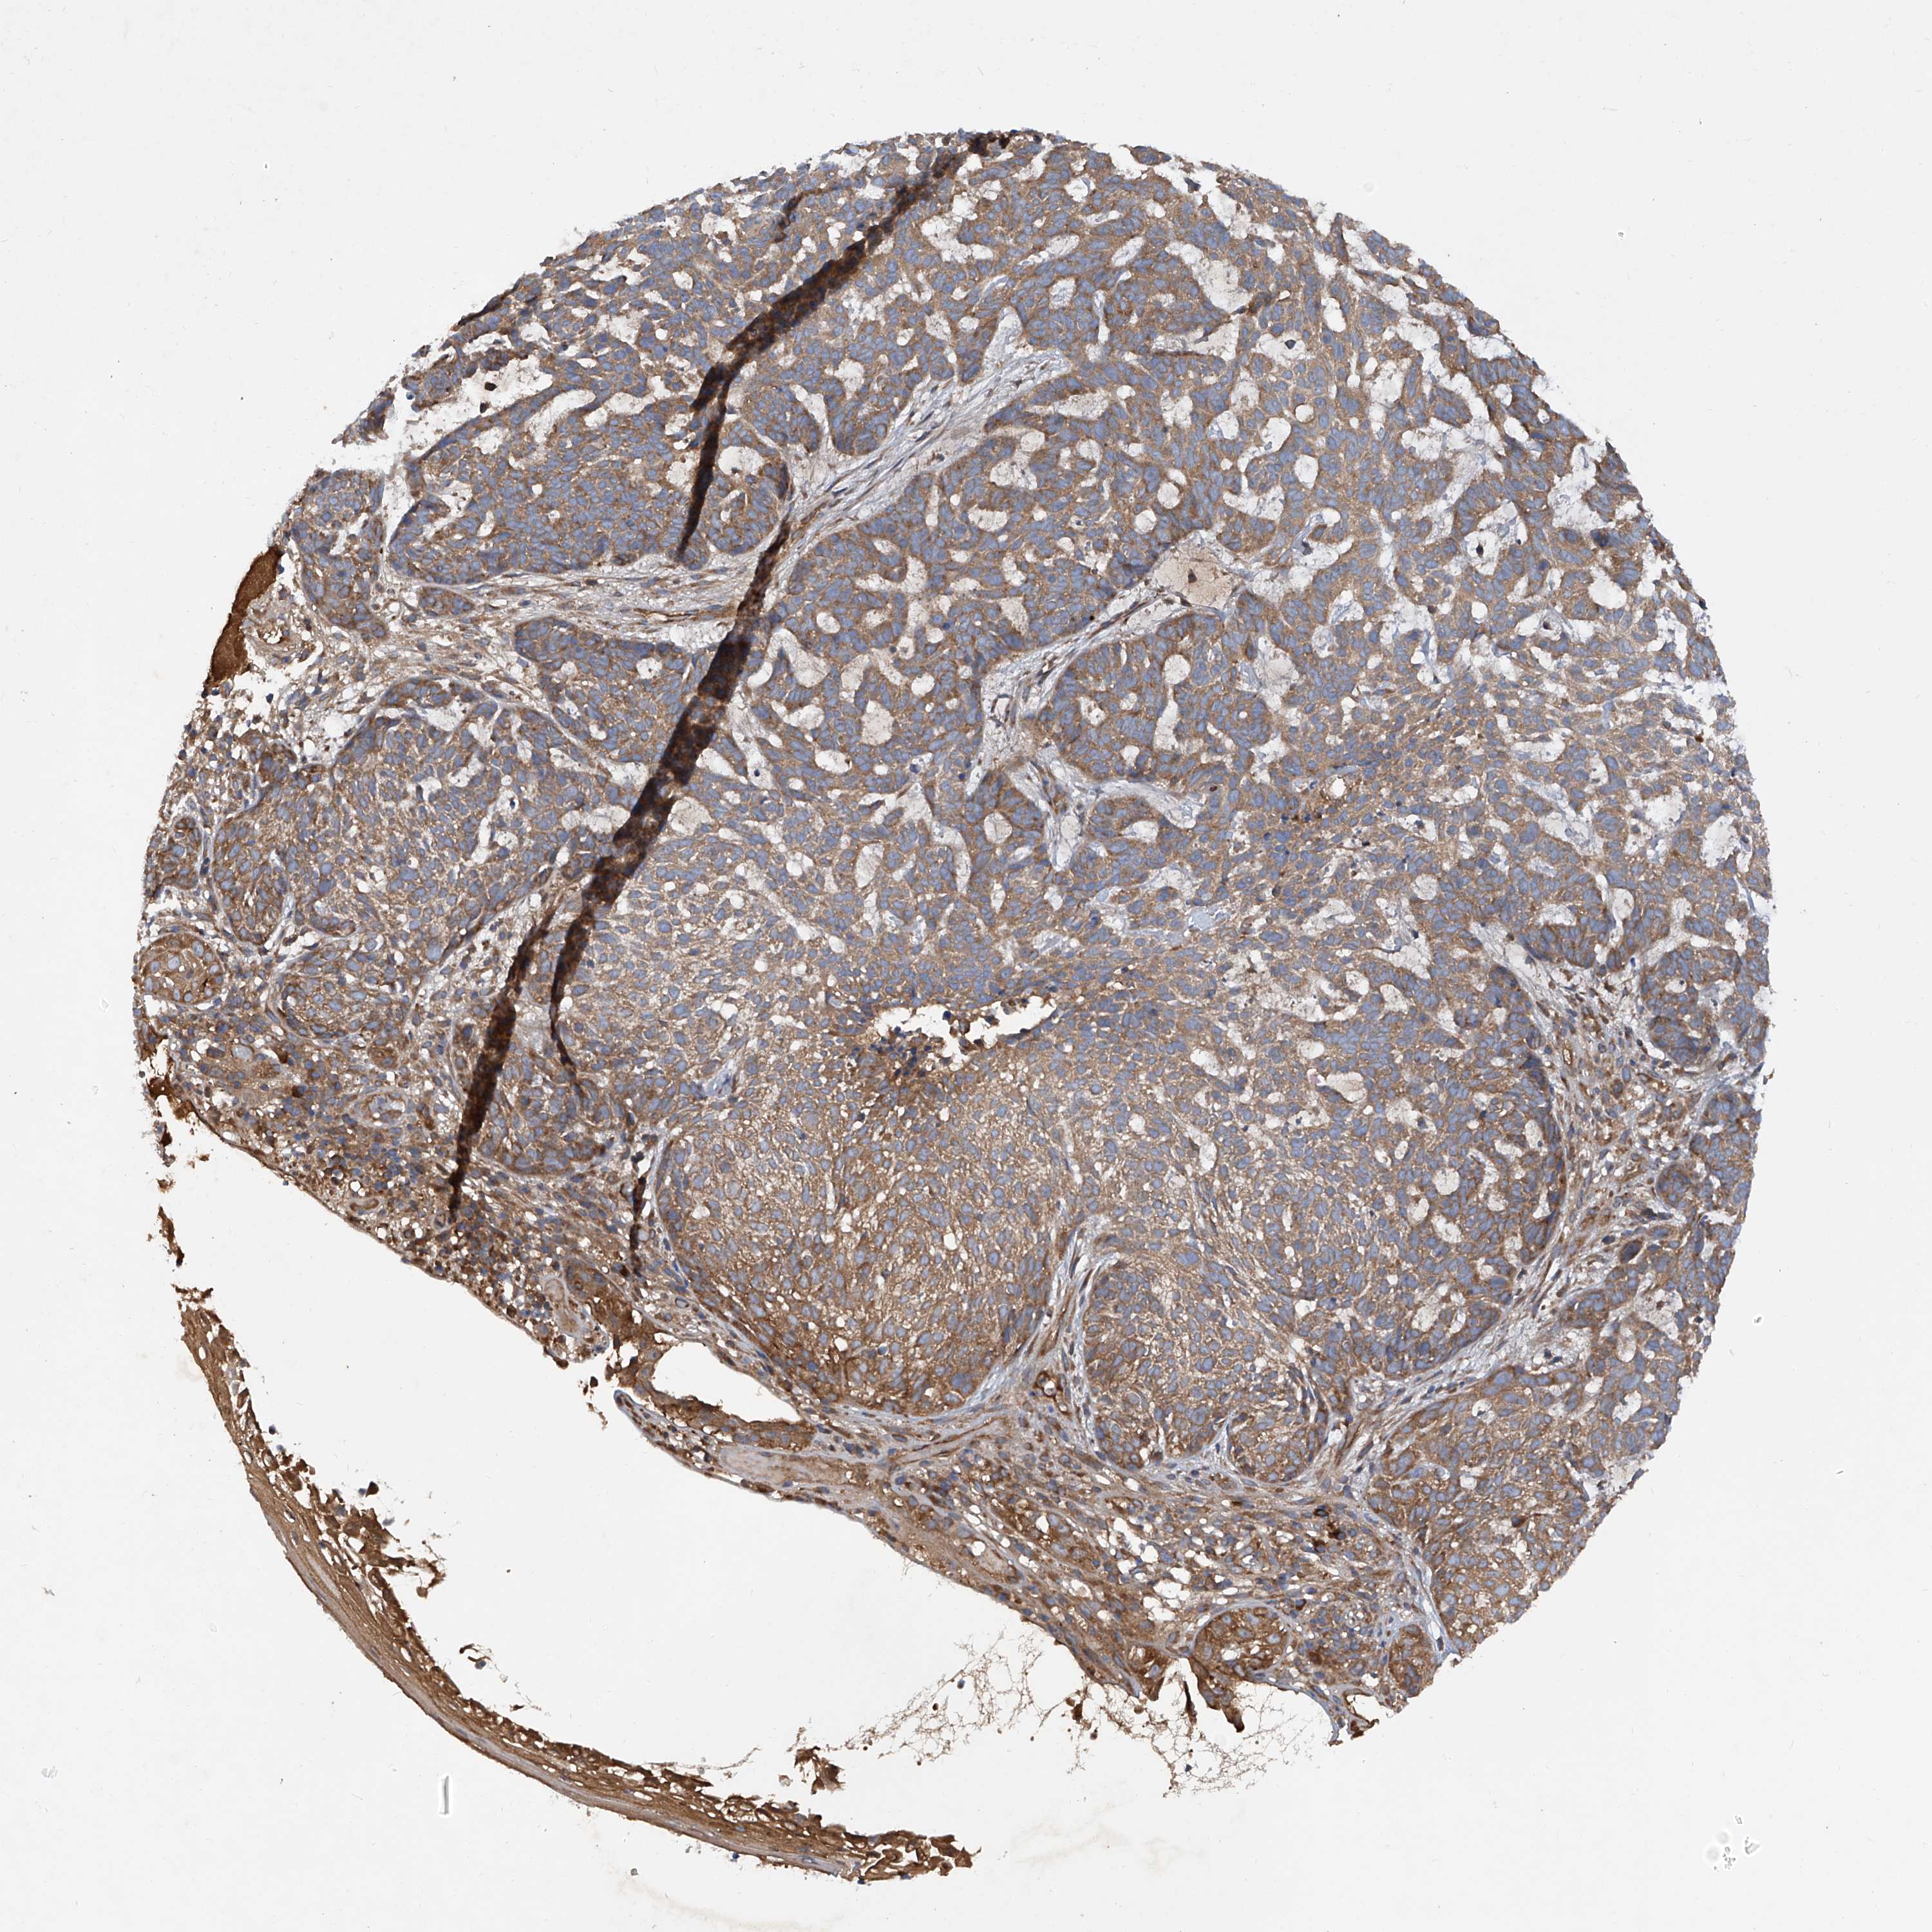

SKIN CANCER - Protein expressioni

A mouse-over function shows sample information and annotation data. Click on an image to view it in a full screen mode. Samples can be filtered based on level of antibody staining by selecting one or several of the following categories: high, medium, low and not detected. The assay and annotation is described here.

Each image is clickable and will lead to virtual microscopy that enables deeper exploration of all samples and also displays staining intensity scores, fraction scores and subcellular localization as well as patient and tissue information for each sample.

Antibody HPA031608

Antibody HPA031609

Antibody HPA031610

Staining

High

Medium

Low

Not detected

Intensity

Strong

Moderate

Weak

Negative

Quantity

>75%

75%-25%

<25%

None

Location

Nuclear

Cytoplasmic/membranous

Cytoplasmic/membranous,nuclear

Squamous cell carcinoma, NOS